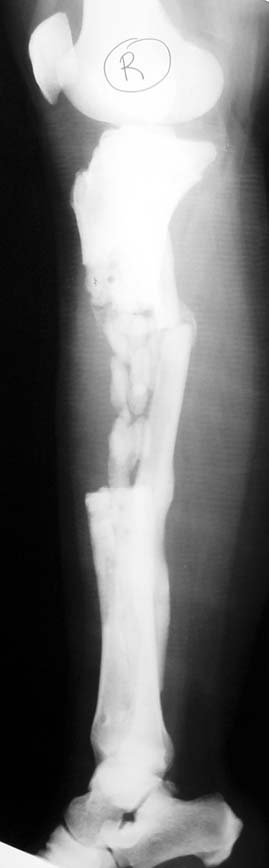

Kronik osteomiyelit, kemik ve yumuşak dokularda nekroza yol açar. Ölü kemik, patojen mikroorganizmalara ev sahipliği yapan bir nidus oluşturur. Konağın savunma sistemleri, mikroorganizmalarla baş etmek için sıklıkla optimal koşullarda değildir. Dolaşım bozukluğu yüzünden enfeksiyon bölgesine antibiyotikler yeterince ulaşamaz. Bu nedenle ölü dokuların ortamdan tamamen uzaklaştırılması gerekir (radikal debridman).

Uygun radikal debridman tüm nekrotik kemik ve yumuşak dokuların çıkartılmasını gerektirir, ve sıklıkla uzuvda instabiliteye neden olur. Kalan kemik ve yumuşak doku defektinin bir şekilde fiksasyonu ve rekonstrüksiyonu gereklidir. İlizarov’un ortaya koyduğu distraksiyon osteogenezi yöntemi, kaynamanın elde edilmesi, deformitenin düzeltilmesi, bacak boy eşitsizliğinin giderilmesi ve segmental defektlerin rekonstrükte edilmesi için başarıyla kullanılmaktadır.